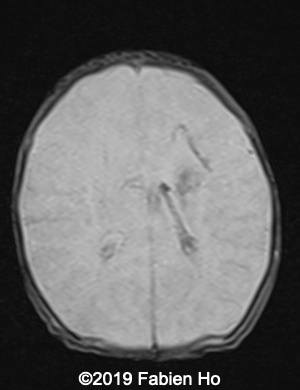

Images 4-11, fetal brain MRI at 28 weeks: the left frontal lesion hence shows DWI hyperintensity, with T2* and T1 peripheral hyperintensity: ischemia with peripheral subacute hemorrhage. Note also that there is an associated blood clot in the left lateral ventricle. There is no obvious mass effect, nor peripheral edema. All these findin>gs are very suggestive of a clastic lesion.

Axial T2*w: T2* sequence is used in this case for its susceptibility to magnetic field inhomogeneity, i.e. to iron deposits for example. It is used to depict hemosiderin, which is roughly oxidized blood, i.e. “aged” blood. Blood MRI signal evolves as time passes.

6

7

Axial T1

8

9